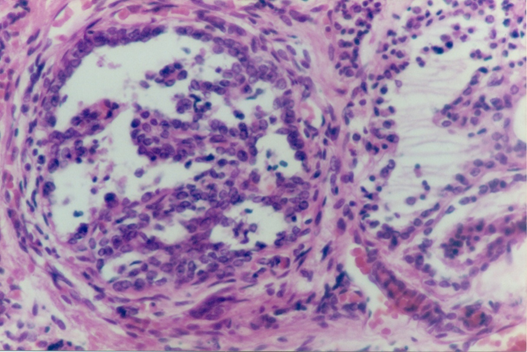

Carcinoma of the thyroid has been classified in this main histological types, papillary carcinoma, follicular carcinoma, medullary thyroid carcinoma and anaplastic carcinoma. Papillary carcinoma type. It is the more frequentlyseen in adults. We have find only one case of this type that presents acharacteristicnodule with papillary pattern (Figure 1). The aspect of nuclei of epithelial cells in no papillary areas are also atypical,looks more like those of the papillary area. Also there is a case with tall epithelial cells,that also have been related to papillary carcinoma (Figure 2).

Figure 2 In papillary carcinoma, a type has been describe with columnar cells.Picture showing that type of lesion.